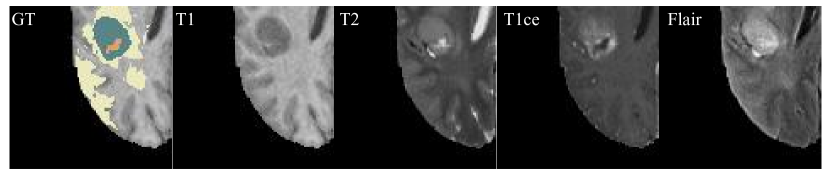

Refer to caption

Figure 1: Images of the four modalities in the brain tumor dataset with the ground truth (GT) segmentation label. Different colors represent different organs: Orange: NCR/NET, Yellow: ED, and Blue: ET.

We can observe from Fig. 4 that in general, the performance of the model with Pmixsubscript𝑃𝑚𝑖𝑥P_{mix}is superior to that without it. When comparing the first and second rows, as well as the first two columns of the third row (cases with three or two missing modalities), we find that the model without Pmixsubscript𝑃𝑚𝑖𝑥P_{mix} struggles to predict NCR/NET, with instances of both missed detections and false detections. Upon observing the predictions of the first and fourth rows, we observe that the model with Pmixsubscript𝑃𝑚𝑖𝑥P_{mix} demonstrates greater accuracy in predicting ED, with smoother ED edges and the ability to predict details. In conclusion, in cases with N𝑁N modalities missing, the model with Pmixsubscript𝑃𝑚𝑖𝑥P_{mix} performs consistently better.

(a) GT

(b) with Pmixsubscript𝑃𝑚𝑖𝑥P_{mix}

(c) without Pmixsubscript𝑃𝑚𝑖𝑥P_{mix}

Figure 4: Qualitative segmentation results of mmFormer with Pmixsubscript𝑃𝑚𝑖𝑥P_{mix} and without Pmixsubscript𝑃𝑚𝑖𝑥P_{mix} on BraTS2018 under all missing scenarios. Below each sub-figure is the Dice. The Dice texts from left to right are WT, TC, and ET. Different colors represent different organs: Blue: NCR/NET, Orange: ED, and Yellow: ET. Captions on the upper-left corners indicate present modalities. Bottom-right corner is the groundtruth labels.